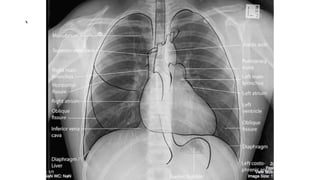

This document provides definitions for various medical terminology related to cardiopulmonary and respiratory systems. It includes terms for different types of breathing difficulties, oxygen and carbon dioxide levels in blood, heart conditions like arrhythmias, heart attacks, and heart failure. Diagnostic tests are also defined such as ECG, CXR, ABG's, pulmonary function tests, bronchoscopy, echocardiograms, CT scans, and cardiac catheterization. Emergency procedures like CPR, intubation, chest tube insertion, and defibrillation are also listed.